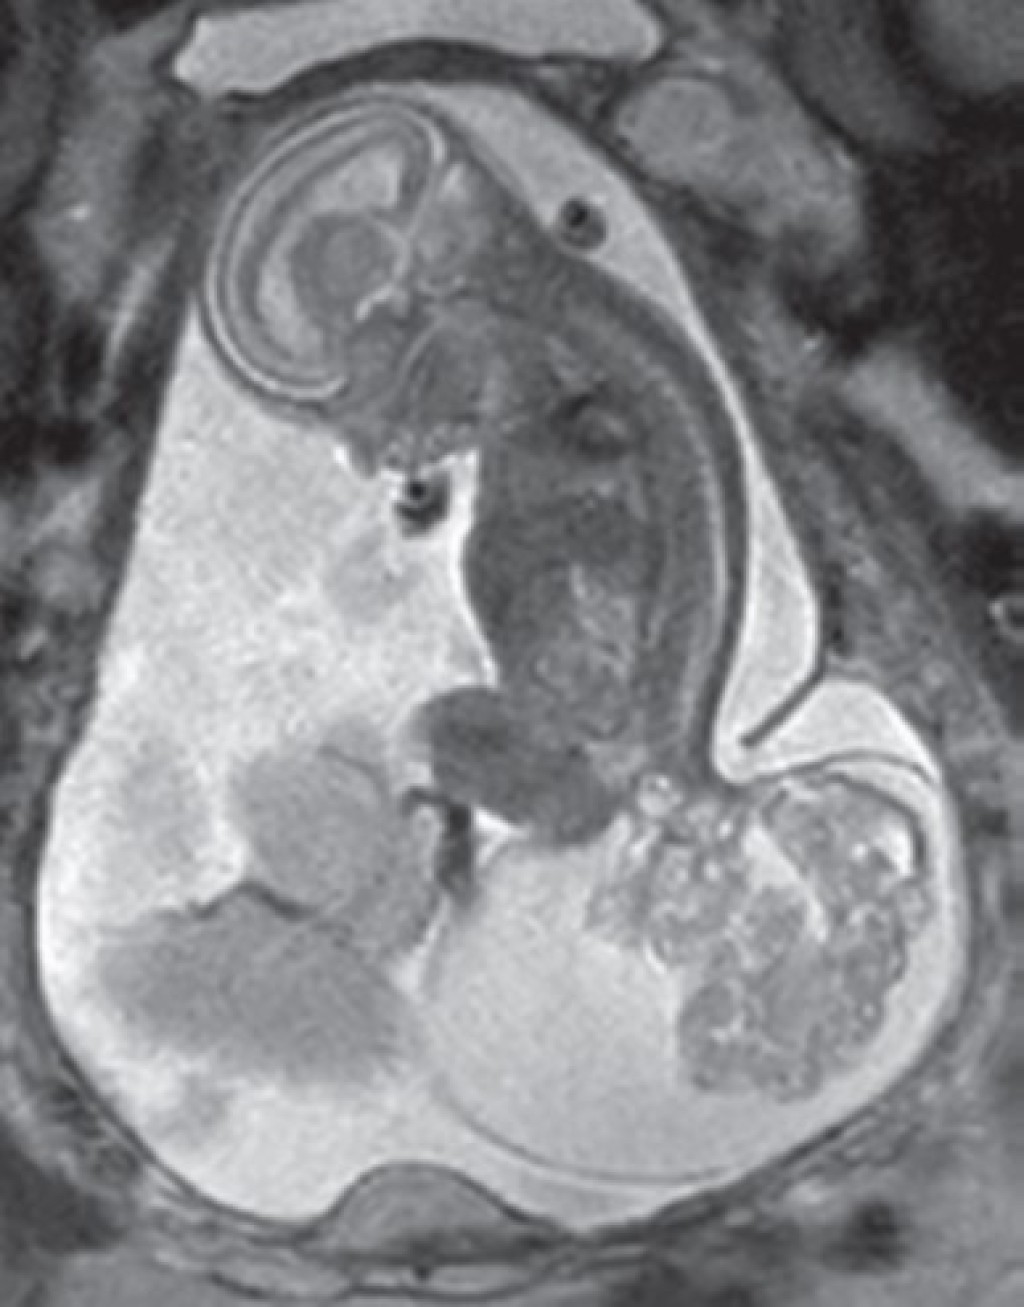

The tumor may be external, growing on the outside of the fetus, or internal, growing inside the body.

- Type III – a significant portion of the tumor is internal, extending into the baby’s abdomen

- Type IV – completely inside the body

- Ultra-fast MRI or low-dose CT for a more detailed view of the mass and fetal anatomy